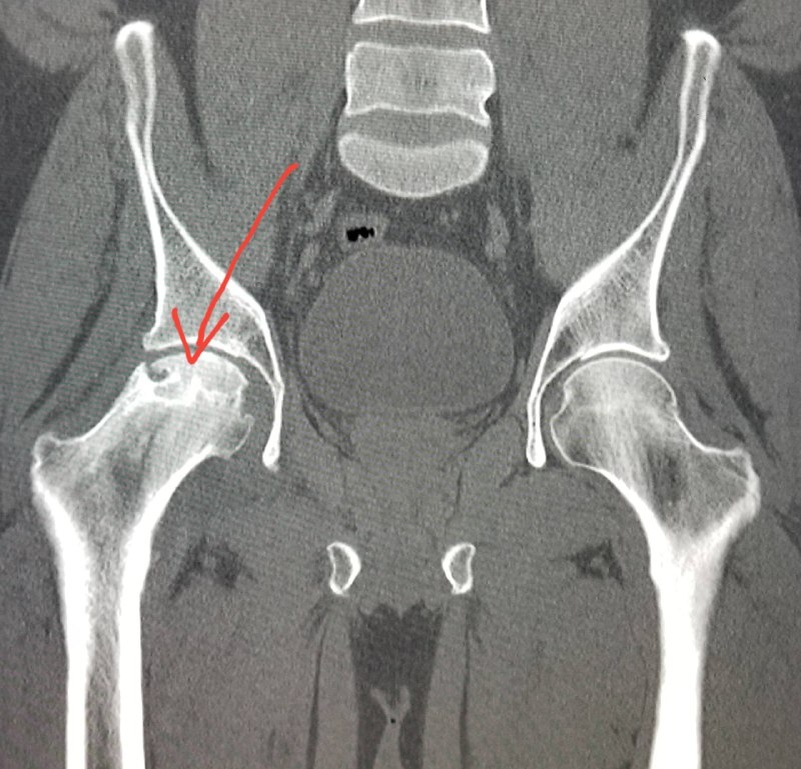

Вероятность развития некроза при незначительных осколочных ранениях оценивается в 5-7%, причем наиболее уязвимыми являются участки с ограниченным коллатеральным кровообращением - головка бедренной кости, проксимальный отдел плечевой кости и таранная кость. В полевых условиях заподозрить начинающийся аваскулярный некроз можно по характерной клинической картине: появление глубоких, "сверлящих" болей, усиливающихся ночью и при нагрузке, постепенное развитие контрактуры близлежащего сустава, локальная болезненность при пальпации и перкуссии кости. Поздним признаком является видимая деформация костного контура.